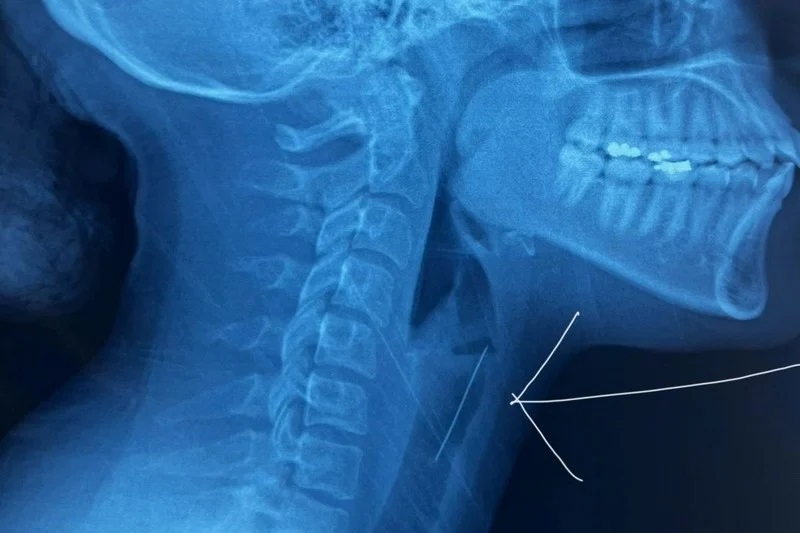

🔍 فحوصات دقيقة تكشف موقع الشوكة

وبعد إجراء الفحوصات الطبية اللازمة، بما في ذلك الأشعة المقطعية، تبين أن الشوكة استقرت في منطقة الحنجرة، مما تطلب تدخلاً جراحياً دقيقاً عبر المنظار الحنجري لإزالتها.

بفضل الله تعالى أولا ثم بجهود فريق طبي متخصص، بقيادة طبيب جراحة الأنف والأذن والحنجرة، وبتنسيق مع طبيب التخدير والإنعاش، تم إجراء العملية تحت تخدير كلي.

وقد استعان الأطباء بكاميرا دقيقة لتحديد موضع الشوكة بدقة وإزالتها بنجاح، مما جنب المريضة مضاعفات خطيرة.